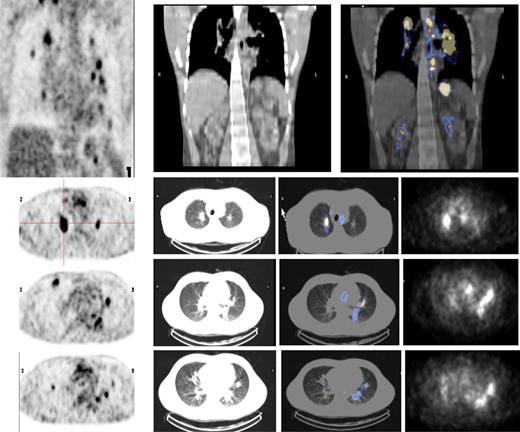

Both HL patients also showed favorable lesion/bone marrow dosimetry estimates after receiving diagnostic 131I-L19SIP, with an absorbed dose of radioactivity to the target lesions—a pulmonary lymphoma lesion (patient HL1) and a left basal pulmonary lesion and a right axillar lymphoma conglomerate (patient HL2)—estimated to be approximately 14 and 22.7 Gy, respectively. The absorbed dose to the red bone marrow was calculated to be 1.3 and 0.85 Gy for HL patients HL1 and HL2, respectively. In HL patient HL1, the SPECT-CT images acquired 12 days after a dose of 5.55 GBq 131I-L19SIP demonstrated selective ED-B FN targeting in multiple parenchymal lung lesions and in enlarged supraclavicular and lumboaortic lymph nodes with all such sites corresponding to high 18F-FDG uptake on baseline PET-CT scans (Figure 6). In the second HL patient (HL2), the SPECT-CT images acquired 12 days after a dose of 3.7 GBq 131I-L19SIP demonstrated selective ED-B FN targeting in multiple enlarged axillar and supraclavicular (both sides), paratracheal, subcarinal, pleural, as well as peritoneal and iliacal (both sides) lymph nodes. ED-B FN–expressing lymphoma lesions were also found in the right and left basal lobes of the lung. All ED-B FN–expressing lymphoma lesions corresponded to high 18F-FDG uptake on baseline PET-CT scans (Figure 7). Both HL patients experienced a partial clinical response according to RESCIST criteria at 1 month after therapy with shrinkage of the sum of diameters of the measurable lymphoma lesions of 44% (134 to 75 mm; baseline to 1 month after treatment) and 39% (417 to 256 mm) for patients HL1 and HL2, respectively. This partial response was confirmed at 2 and 3 months after 131I-L19SIP therapy for both HL patients. The 3 lymphoma patients did not experience any acute toxicity during or after 131I-L19SIP therapy. Mild and transient thrombocytopenia was observed in both HL patients, but not in the SLL NHL patient, with a nadir of 22 and 52 × 109 platelets/L for patients HL1 and HL2, respectively, at 6 weeks after 131I-L19SIP injection.

18F-FDG PET scans and 131I-L19SIP SPECT-CT images from an advanced Hodgkin lymphoma patient (HL1).18F-FDG PET scans show intense glucose metabolism in multiple enlarged mediastinal lymph nodes, intrapulmonary lesions (leftmost column, first 4 images; intrapulmonary lesion marked), as well as in lumboaortic lymph nodes (leftmost image in lowest row). The same patient received intravenous injections of 185 MBq and, subsequently, 5.55 GBq 131I-L19-SIP. SPECT-CT coronal (top right panel) and transaxial images of the thorax (rows 2-4) as well as the upper abdomen (lowest row) are shown, demonstrating selective uptake of 131I-L19SIP into the 18F-FDG–labeled lymphomatous lesions.